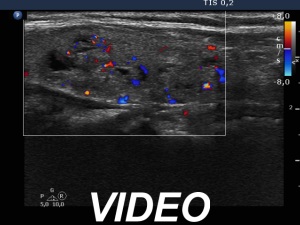

Ultrasonography. The thyroid was echonormal and had multiple moderately hypoechoic and hyperechoic nodules which showed various degrees of cystic degeneration. The largest nodule in the right lobe was dominantly cystic and presented with minimally hypoechoic solid part which included hyperechoic figures. The largest nodule in the left lobe had irregular margins.